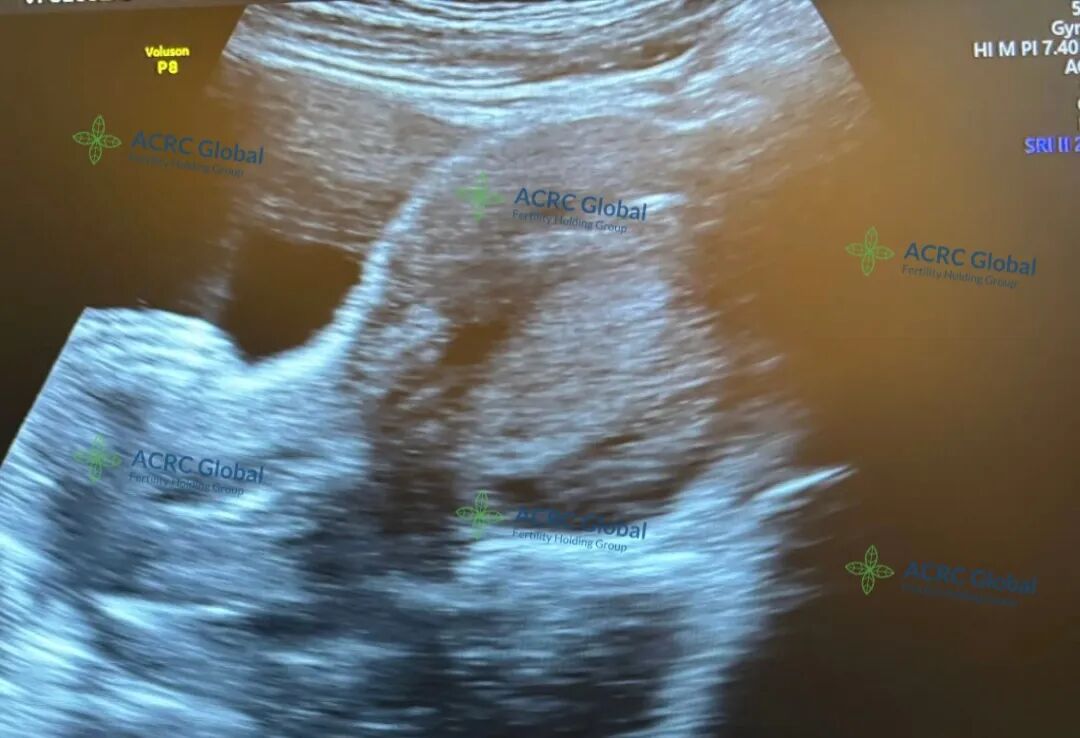

来自佛罗里达州的爱妈S终于迎来了她的移植日!她是一位单身妈妈,而这次与她匹配的也是一位独立勇敢的单身准妈妈。准妈妈之前因为专注于事业,不知不觉错过了最佳生育时机,如今希望通过爱妈S的帮助,实现成为母亲的梦想。期待几天后的验孕能传来喜讯!

爱妈S顺利完成了这次移植,开启了新的孕期旅程!准妈妈常年生活在香港,一直有个温暖的愿望,希望拥有一个热热闹闹的大家庭。她之前在诊所冷冻了10个胚胎,已经通过两位爱妈迎来了大宝和二宝,两个宝宝都非常健康可爱。这次她也希望在爱妈S的帮助下,继续迎接新的小生命的到来。我们也将一路陪伴,继续为她匹配合适的爱妈,帮助她一步步实现大家庭的梦想。愿这次胚胎顺利着床,好消息很快到来!